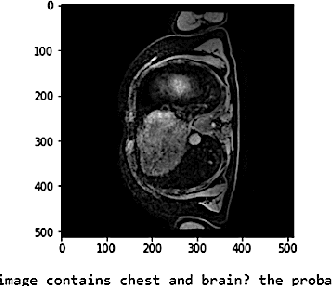

Abstract:Vision-language models have emerged as a powerful tool for previously challenging multi-modal classification problem in the medical domain. This development has led to the exploration of automated image description generation for multi-modal clinical scans, particularly for radiology report generation. Existing research has focused on clinical descriptions for specific modalities or body regions, leaving a gap for a model providing entire-body multi-modal descriptions. In this paper, we address this gap by automating the generation of standardized body station(s) and list of organ(s) across the whole body in multi-modal MR and CT radiological images. Leveraging the versatility of the Contrastive Language-Image Pre-training (CLIP), we refine and augment the existing approach through multiple experiments, including baseline model fine-tuning, adding station(s) as a superset for better correlation between organs, along with image and language augmentations. Our proposed approach demonstrates 47.6% performance improvement over baseline PubMedCLIP.